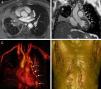

Un varón de 57años de edad presentó tos, disnea y circulación colateral en la pared torácica. La resonancia magnética (RM) mostró una masa mediastínica en el hilio pulmonar derecho que obstruía casi por completo la vena pulmonar superior derecha, con obstrucción de la vena cava superior (VCS), atelectasia del lóbulo medio y circulación colateral exuberante para el retorno venoso, especialmente en las venas pericardiofrénicas izquierdas, que eran varicosas, y circulación colateral en las paredes torácica y abdominal (fig. 1). La biopsia evidenció una mediastinitis fibrosante.

A)Imagen de RM axial con ponderación T1, en la que se observa una masa en el hilio pulmonar derecho. El bronquio principal está envuelto por la masa (no mostrado), y ello causa una atelectasia del lóbulo medio. B)La imagen de RM coronal muestra unas venas dilatadas (varices pericárdicas) a lo largo de la superficie lateral del pericardio (flechas). Hay también una atelectasia del lóbulo medio. C)Imagen de RM reformateada en 3D, que muestra venas pericárdicas dilatadas (varices pericárdicas: flechas). D)Imagen de RM reformateada en 3D, que muestra una circulación colateral en las paredes torácica y abdominal.